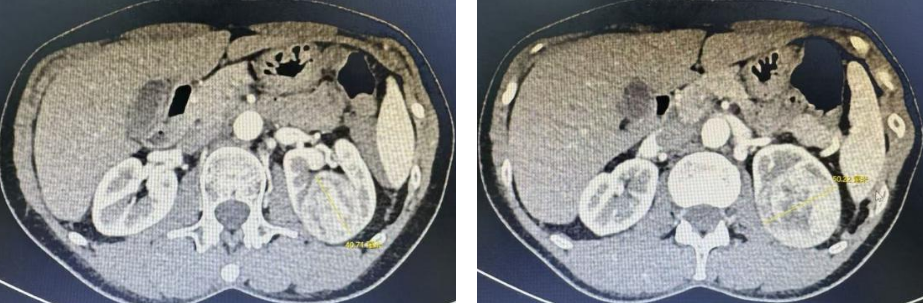

精雕细琢 肾门禁区的“血管守护战”

在复杂肾癌病例中,肾门部中央型肿瘤因“位置险要”,被称为“保肾手术的禁区”。其中一例病例的患者体内瘤体紧密包裹肾动脉主干,手术操作空间仅毫米级,传统开放或腔镜手术极易损伤血管,引发肾脏缺血坏死或致命性大出血。

面对这一挑战,团队依托机器人手术系统的核心优势,10倍放大三维视野以及7个自由度的器械腕部灵活转向能力,实现“雕刻式”精细分离。术中,王子琦教授带领王宏磊副教授和宋洪戬医师,沿血管外膜与肿瘤包膜之间的微小间隙逐层解剖,如同在“生命通道”上进行精准拆解。最终将肿瘤从肾动脉表面完整剥离,重要血管结构毫发无损,完美达成“根治肿瘤不损伤血管”的高难度目标。

肾肿瘤影像